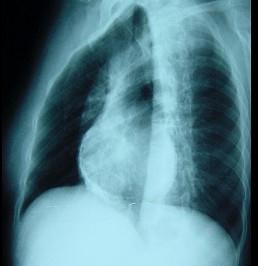

女性,46岁。间断胸痛4年,胸闷2年,外院诊断为“风湿性心脏病”。入院查体:血压110/65mmHg,颈静脉无充盈,心律75次/分,未闻及杂音,双下肢浮肿...

问题 女性,46岁。间断胸痛4年,胸闷2年,外院诊断为“风湿性心脏病”。入院查体:血压110/65mmHg,颈静脉无充盈,心律75次/分,未闻及杂音,双下肢浮肿,肝脏肋下2cm。 该病的病理和病理生理为 ( )